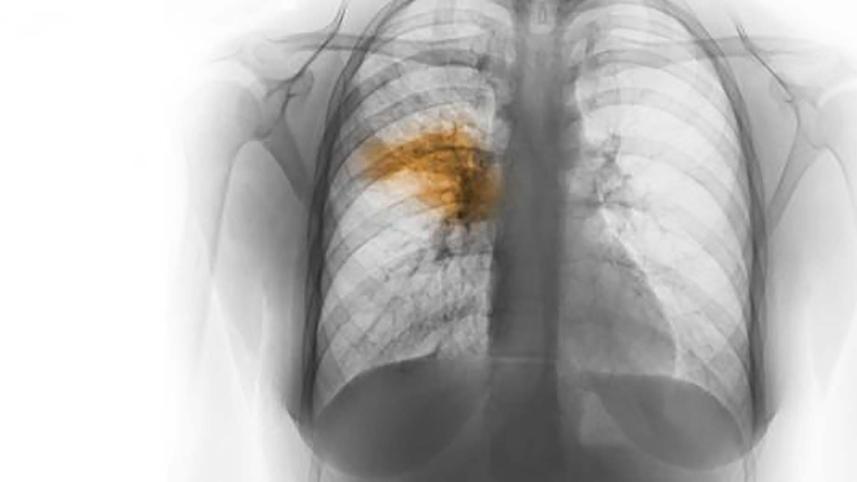

Fifteen children died of pneumonia at hospitals in Khagrachhari, Rangamati and Bandarban in the last two weeks, said doctors.

"Seven children died due to the disease (pneumonia) in the last 14 days," said Dr Bappi.

Meanwhile, Showkat Akbar Hossain, resident medical officer (RMO) of Rangamati Sadar Hospital, said, "Six children died of pneumonia and cold complications in Rangamati Sadar Hospital in the last two weeks."

Bandarban Sadar Hospital RMO Ziaul Haider said, "A two-month-old baby died of pneumonia at the hospital recently."